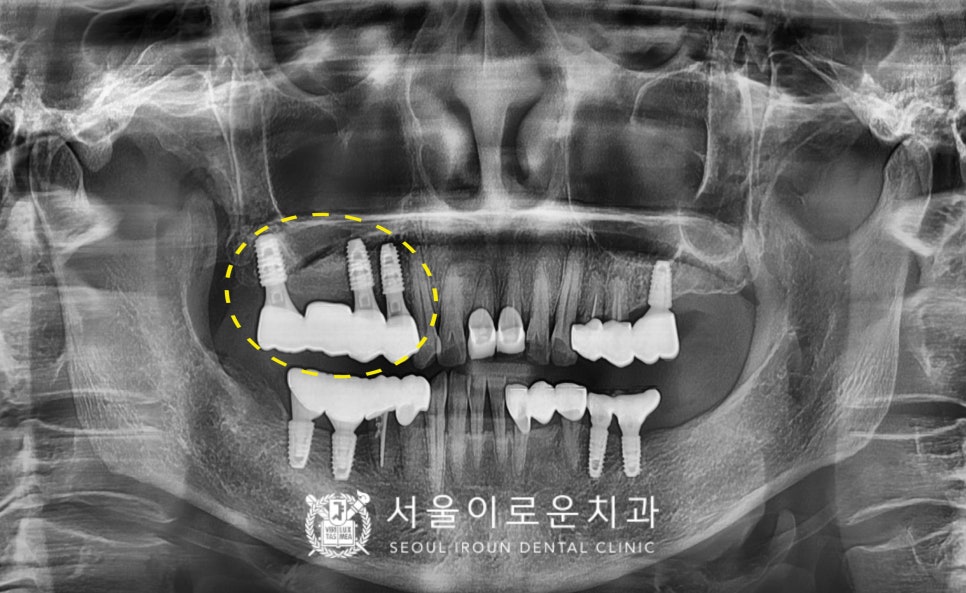

치조정 접근법을 활용한

상악동 거상술 및 뼈이식을 진행한 후,

임플란트까지 동시에 식립을 도와드렸습니다.

그리고 뼈가 단단하지 않아

외부 힘을 가능한 받지 않고,

뼈와 임플란트가 단단히 붙을 수 있게

픽스처가 잇몸 하방으로 묻히도록

커버스크류라는 뚜껑으로 체결하여

마무리해주었답니다.